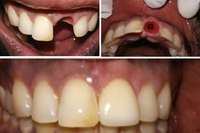

Single Tooth Implant

Single tooth implants replace a missing tooth without impacting neighboring teeth. This highly predictable solution acts like a natural root, supporting a crown while preserving the surrounding bone structure and teeth integrity.